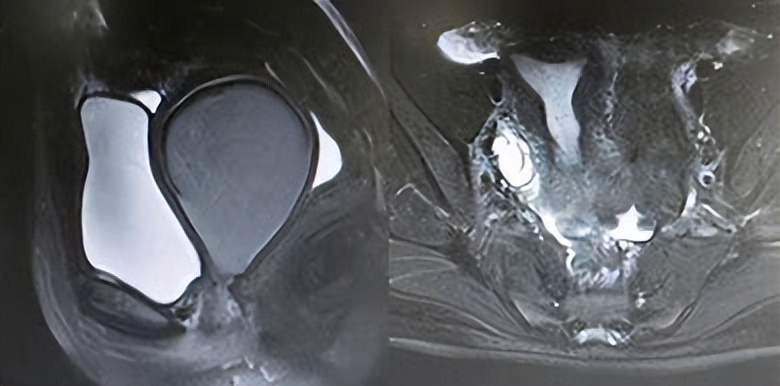

在医学角度上,“真石女”的病情主要表现为先天性阴道闭锁、阴道过窄或完全无阴道,子宫、卵巢缺失。这一般与以下两种疾病有关:①Mayer-Rokitansky-Küster-Hauser (MRKH) 综合症;②Androgen Insensitivity Syndrome (AIS)。

大部分“真石女”往往患有一种叫做MRKH综合征的疾病,即先天性无子宫、无阴道,这是一种先天性结构异常,在目前的医疗水平下,暂无法使其恢复。

MRKH综合征的病因尚未完全明确,但目前认为它主要与胚胎发育过程中苗勒管的异常发育有关。

在胚胎发育过程中,苗勒管是形成女性生殖系统的重要结构,它会分化为子宫、输卵管和阴道。对于患有MRKH综合征的女性来说,可能是苗勒管的发育出现了问题,导致子宫或阴道的缺失或发育不良。